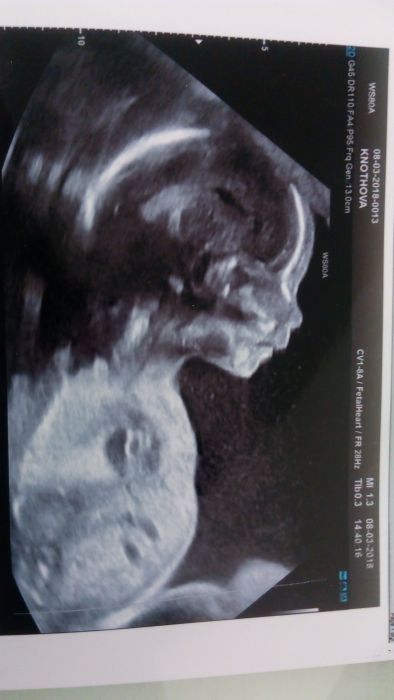

Vcera jsem byla na 2.screeningu vše v pořádku Malej vazi 400g.nic jsem neplatila.i hezkou fotku mame